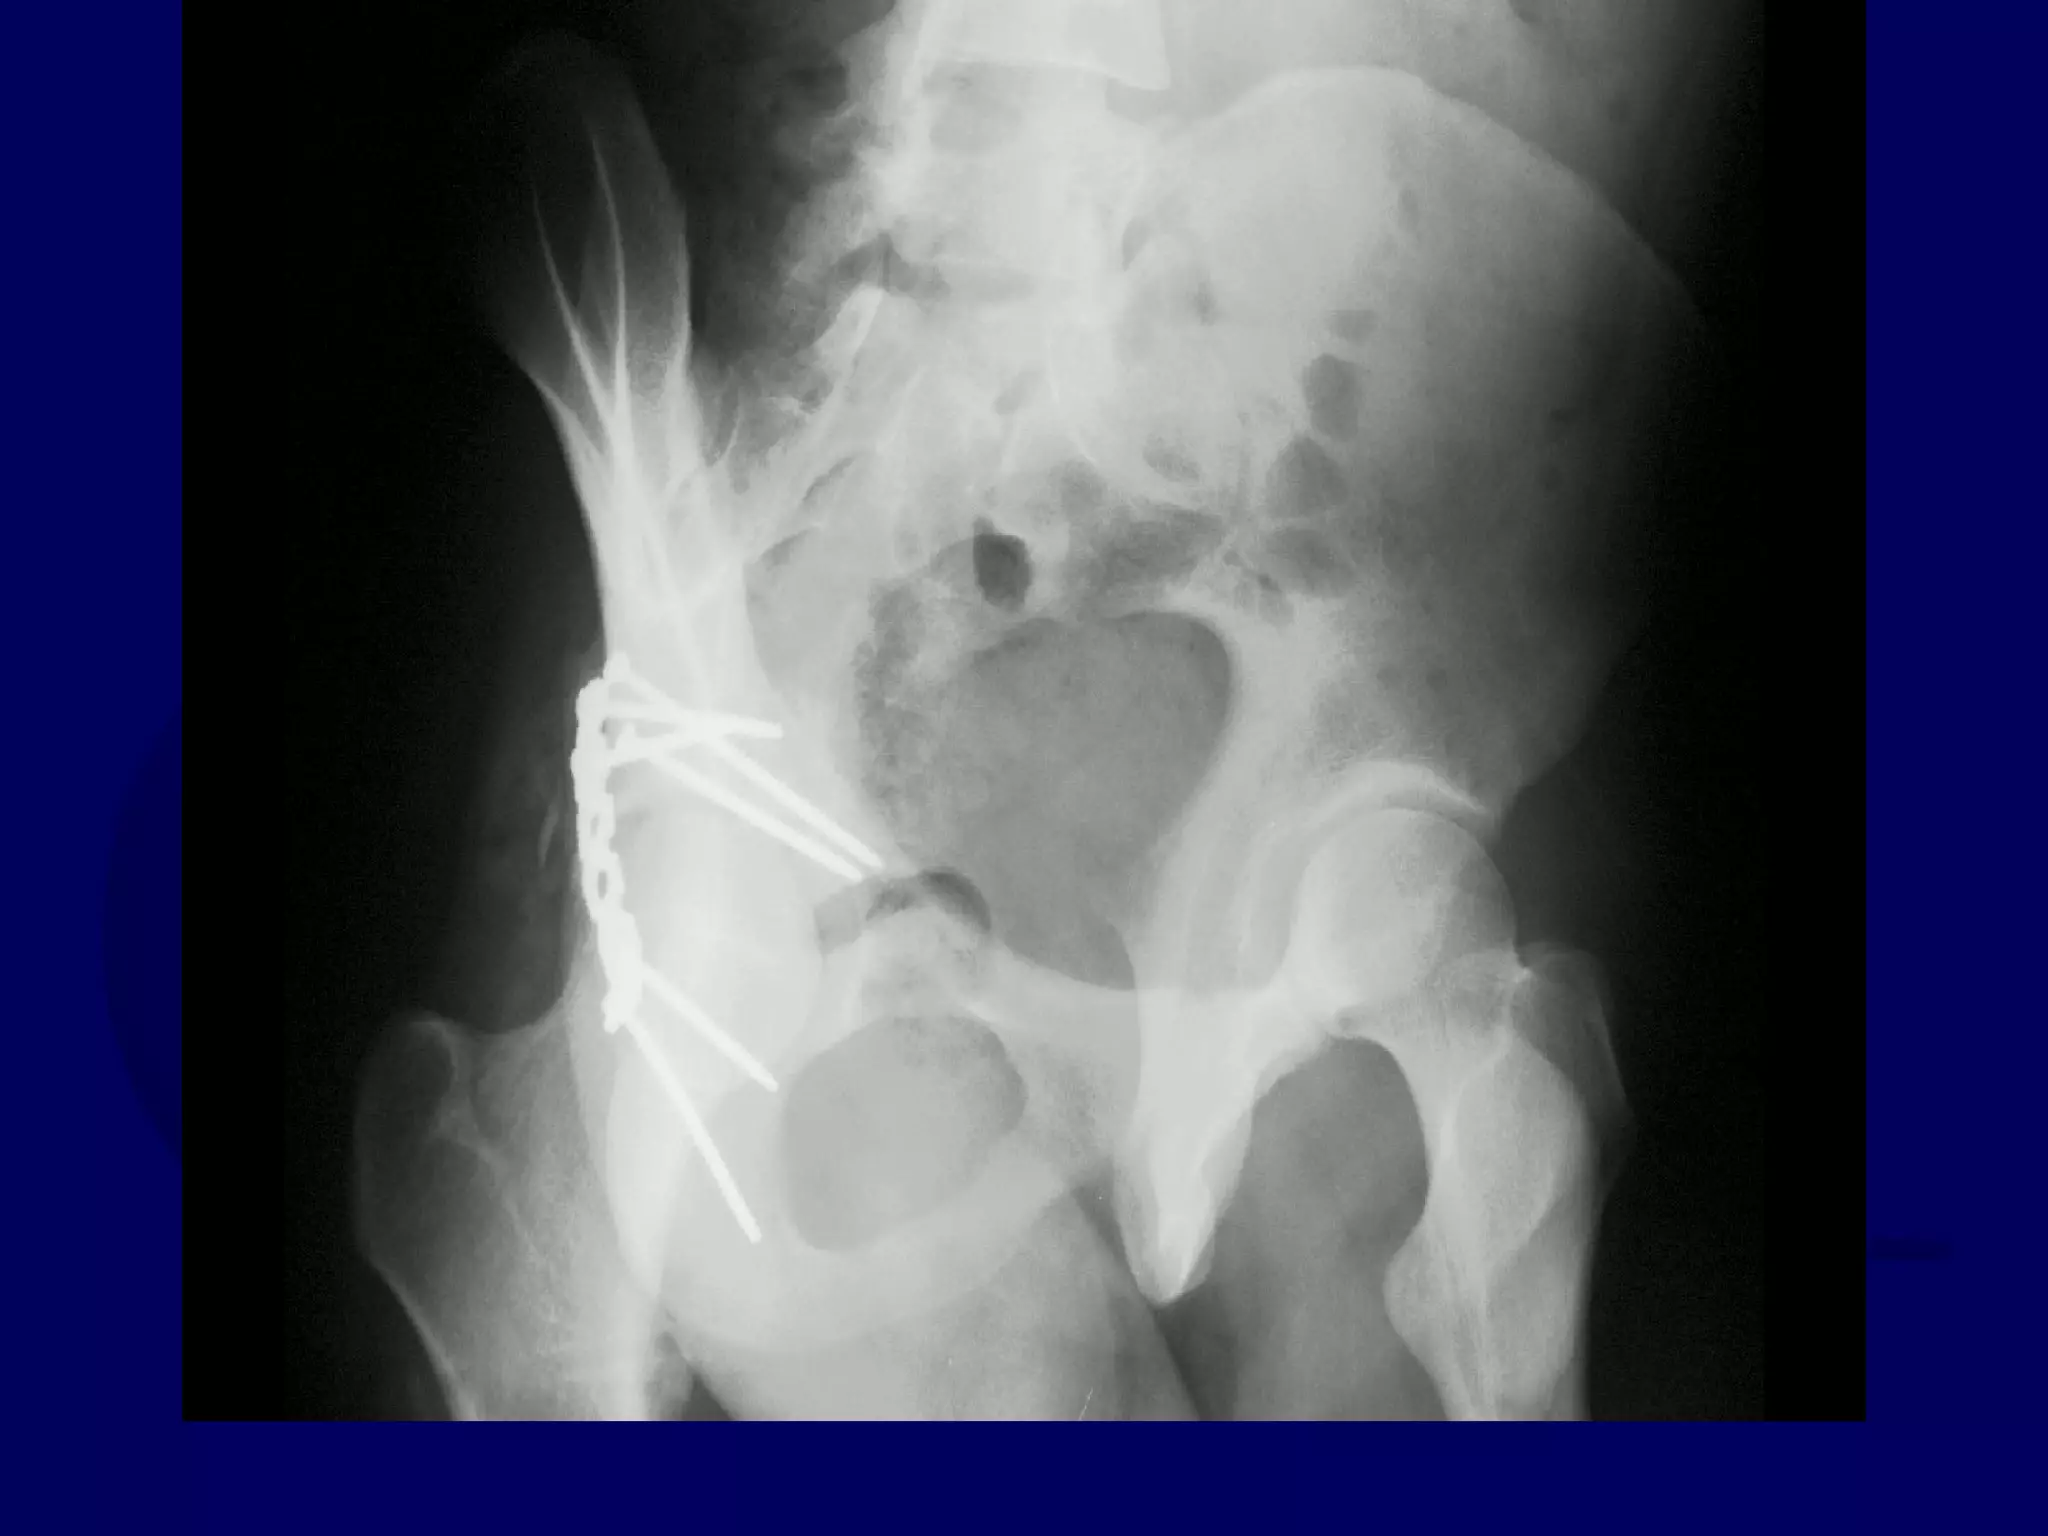

Special Case

“T-Type” Acetabular Fracture

Proximal Femur Fracture

14 y.o. Male

Sequential K-L / Ilioinguinal

Approaches

P.J. 00.12.16

Initial Kocher-Langenbeck

Approach

P.J. 00.12.18

Subsequent Ilioinguinal

P.J. 00.12.22